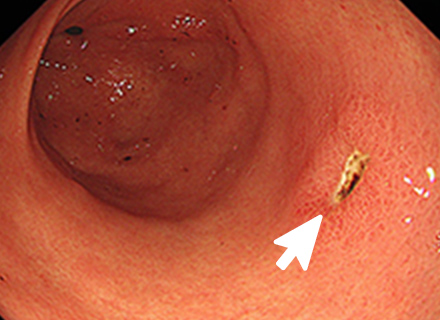

大腸ポリープまたは早期大腸がんの内視鏡治療

良性のポリープや早期がんの中でも粘膜だけにとどまっているもの、粘膜下層へわずかに広がっているものが内視鏡治療の適応となります。 小さなポリープに対しては、鉗子でつかみながら高周波電流を用いて病変の根もとを焼き切ります(ホットバイオプシー)。 茎のあるポリープに対しては、輪の形のスネアを茎の部分でしめ、高周波電流を用いて切断します(ポリペクトミー)。 茎のない病変に対しては、内視鏡的粘膜切除術(EMR)や内視鏡的粘膜下層剥離術(ESD)などを行います。